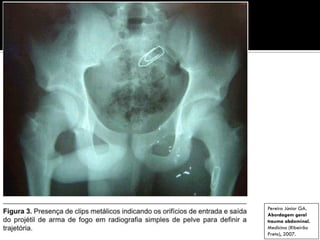

 Trauma PAF

 Raio X simples da pelve

Pereira Júnior GA.

Abordagem geral

trauma abdominal.

Medicina (Ribeirão

Preto), 2007.